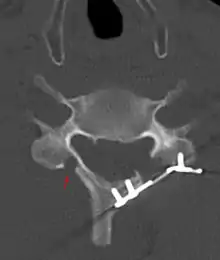

الأشعة المقطعية لجراحة التضيق القطني من الفقرة العنقية